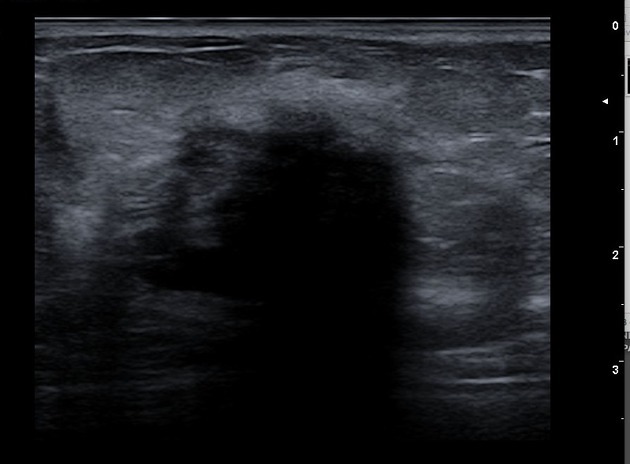

The affected side (left side here) show diffuse, relatively ill-defined, echogenic breast fat tissue and increased colour flow Doppler, and enlarged lymph nodes in the axilla, with no evidence of focal skin thickening or traction, well-defined mass, or nearby extra-breast tissue invasion.

The dilated lactiferous ducts are of similar appearance bilaterally, without evidence of wall thickening or internal echogenic component or debris.

Comparison of the normally appearing, non-affected (right side here) breast and axilla demonstrate the difference in echogenicity, architecture, axillary lymph nodes, (shown), and vascularity (right side not shown).

Ultrasound

primary modality of choice

abscess: irregular, hypoechoic to anechoic mass with fluid and debris and posterior acoustic enhancement

mastitis: ill-defined, hypoechoic region

periductal inflammation

guidance for abscess drainage